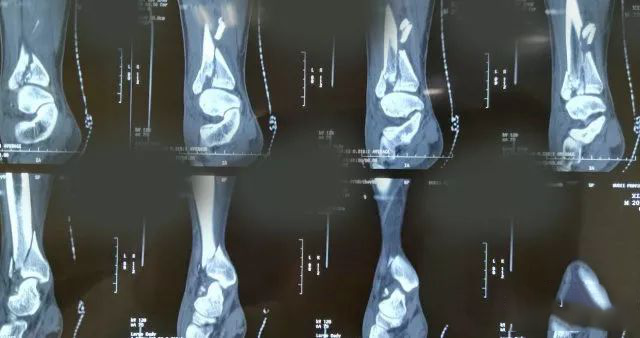

一起来看一个病例:男,20岁,摔倒右踝3天,体格检查示右小腿下段肿胀压痛,活动受限,运动感觉可,诊断为右侧 Pilon骨折。X片及CT三维图如下,欢迎投票并在评论区附上理由。